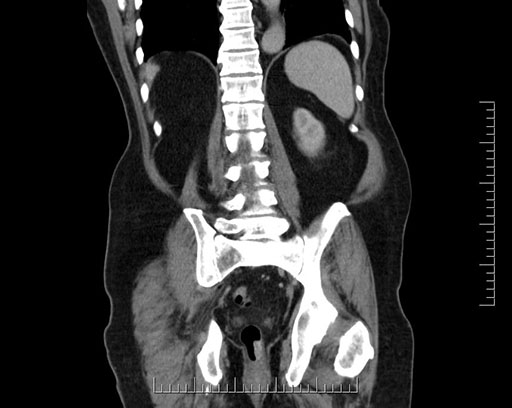

Axial - stented